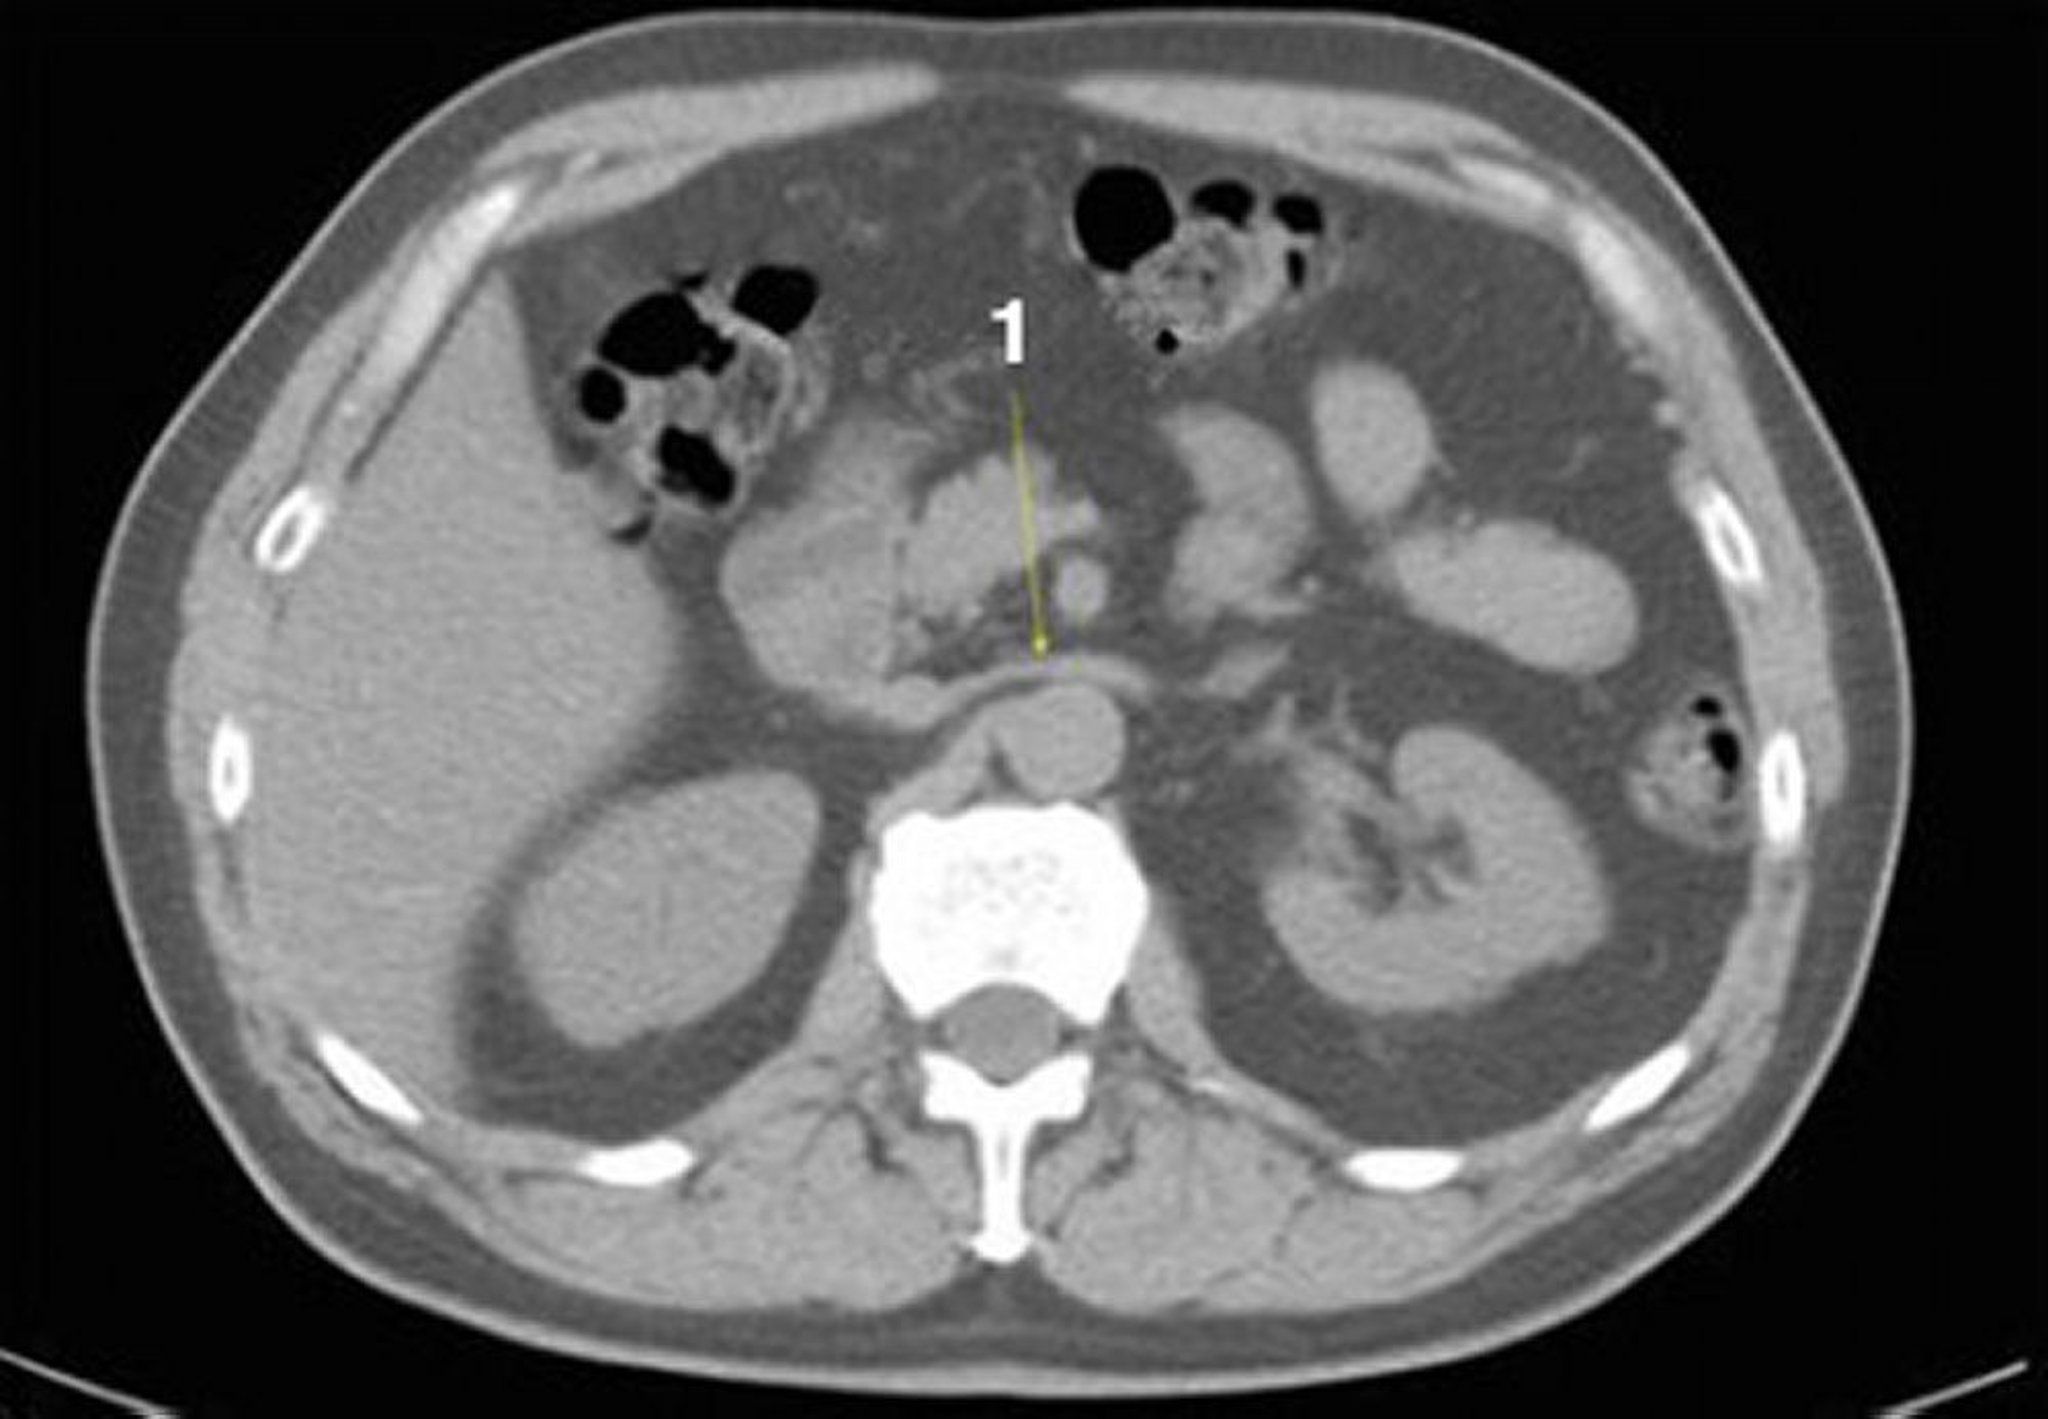

CT-Scan von Abdomen und Becken mit normaler Anatomie ohne Kontrastmittel (Folie 12)

1 = linke Nierenvene.